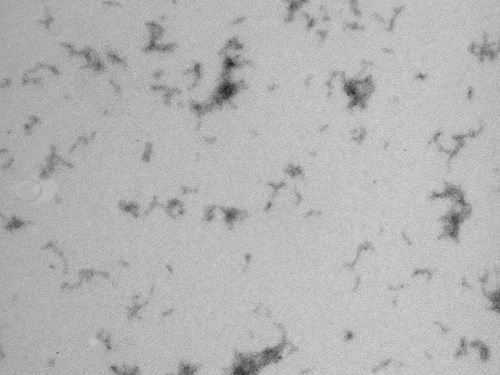

One of the hallmarks of AD is the aggregation of the amyloid-beta protein, a process that results in the formation of plaques, which are observed in the brains of those affected by this disease. These plaques comprise fibrillar aggregates of the amyloid-beta protein, known as amyloid fibrils.

Given this observation, scientists initially proposed that amyloid fibrils were likely to be the causative agents of the disease. Later, however it was observed that there was only a relatively weak correlation between the levels of amyloid plaques and the severity of the dementia. These findings led to new hypotheses that much smaller aggregates, formed before the development of the fibrils, are responsible for the neurodegenerative process. “What remains to be determined is which of the multitude of aggregates formed by the amyloid-beta protein are the most toxic and how they exert such toxicity. This knowledge gap is one of the reasons why clinical trials to stop the progression of the disease have so far failed,” explains Dr Carulla.